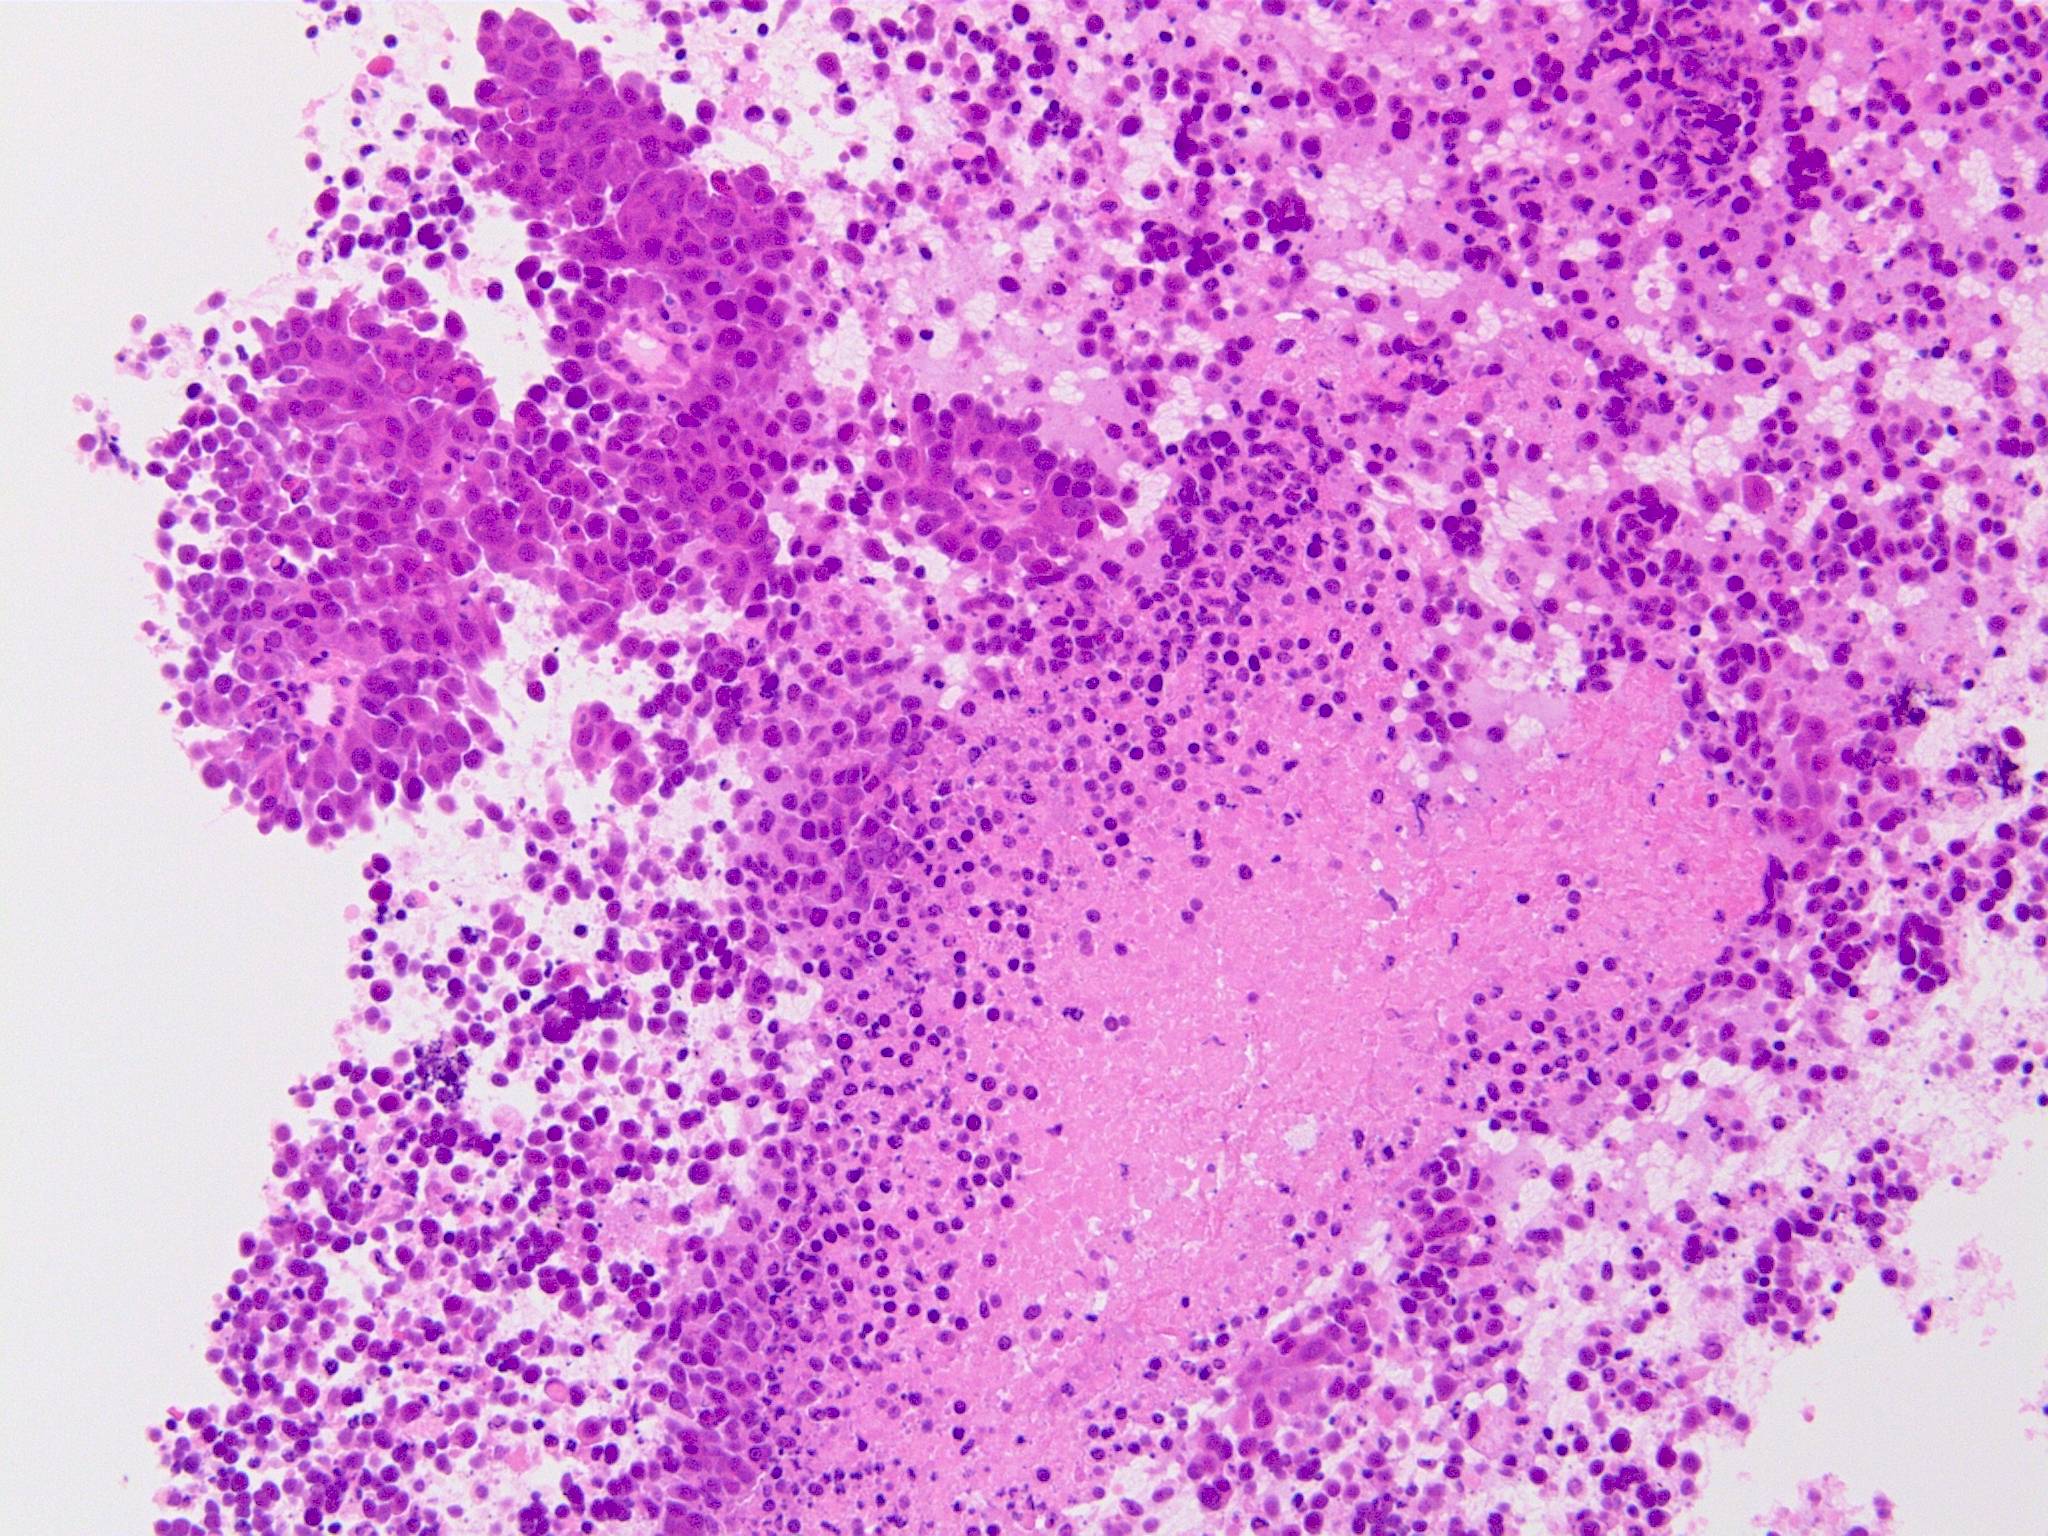

IWT case: 30歳代半ば,女性; 喫煙歴:15本/日,20歳から現在まで

当院を受診する4か月前から前胸部違和感を自覚していた. 2か月前から喘鳴を伴う咳嗽があり近医を受診.気管支喘息が疑われ加療されたが症状は改善しなかった.

経過観察中に施行された胸部CTでは左肺癌が疑われた.精査加療目的に当院呼吸器内科を紹介受診.

血液検査:腫瘍マーカー cytokeratin 19の上昇あり[14 (>3.5ng/mL)],ProGRP, CEA, CA19-9の上昇なし

CT画像:左肺から縦隔に及ぶ腫瘍(肺は単独病変. 肺内転移なし.),乳腺腫瘤,子宮腫瘤, 多発肝腫瘤あり.

処置: 気管支内視鏡検査で,1.左肺腫瘍からTBB (VS1),2.腫瘍と一塊になったリンパ節からEBUS-TBNA (VS2),を施行された.

CT画像および肺腫瘤生検組織